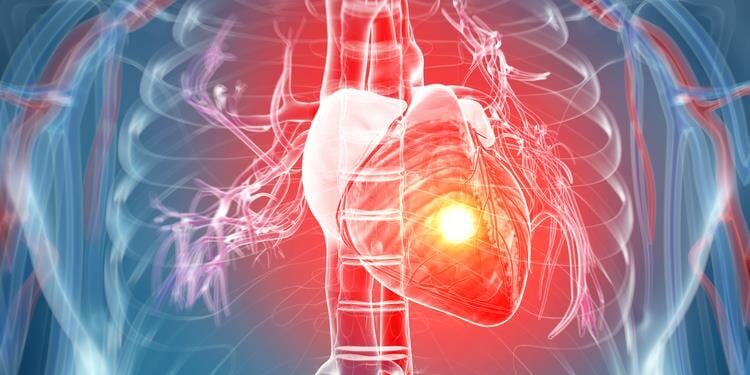

Een nieuwe micronaaldpleister levert een therapeutisch molecuul rechtstreeks aan beschadigd hartweefsel, waardoor het hart wordt hersteld na een hartaanval. De behandeling moedigt immuuncellen aan om in een genezende staat te komen en verbetert tegelijkertijd de communicatie tussen cellen die de bloedstroom controleren en herstellen. De patch is ontwikkeld door een onderzoeksteam onder leiding van Dr. Huang, assistent-professor bij de afdeling Farmaceutische Wetenschappen van de Texas A&M University. De pleister maakt gebruik van een gespecialiseerd micronaaldsysteem om interleukine 4 (IL4) rechtstreeks in beschadigd hartweefsel af te leveren, waardoor de algehele hartfunctie wordt hersteld en verbeterd.

Wanneer een hartaanval optreedt, wordt de bloedtoevoer naar delen van het hart onderbroken. Cellen in het getroffen gebied verliezen zuurstof en voedingsstoffen en beginnen af te sterven. Het lichaam reageert door littekenweefsel aan te maken om het hart te stabiliseren, maar dit litteken kan niet samentrekken zoals gezonde spieren. De nieuwe pleister is ontworpen om dit proces te onderbreken door IL4 rechtstreeks op de plaats van het letsel af te geven, waardoor immuuncellen worden aangemoedigd om over te schakelen naar een genezende staat en littekenvorming te beperken.

Het onderzoeksteam ontdekte dat de pleister schadelijke ontstekingssignalen afkomstig van endotheelcellen verminderde en de activiteit in een signaalroute genaamd NPR1 verhoogde, wat de gezondheid van de bloedvaten ondersteunt en de algehele hartfunctie verbetert. Momenteel vereist het aanbrengen van de pleister nog een open borstoperatie, maar Dr. Huang hoopt een versie te ontwikkelen die via een klein buisje kan worden ingebracht, waardoor de behandeling in de echte medische omgeving veel gemakkelijker zou worden.

De nieuwe pleister vermijdt het probleem van ongewenste effecten in andere organen door IL4 geconcentreerd te houden in het gewonde gebied in plaats van zich door het lichaam te verspreiden. Hierdoor wordt alleen het hart getarget en wordt de communicatie tussen verschillende celtypen verbeterd, wat een belangrijke rol speelt bij herstel op de lange termijn. Het onderzoeksteam hoopt de planning en oplevering van de pleister verder te optimaliseren en te verbeteren.